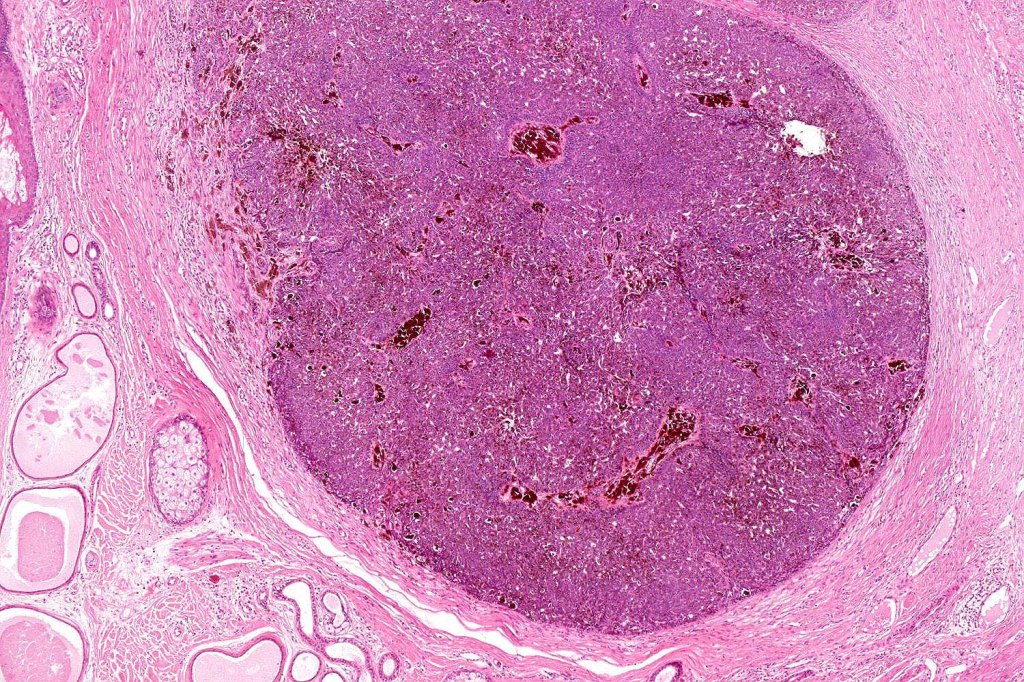

•May be complicated by a wide range of tumors (which are often multiple) including trichilemmoma, trichoblastoma, SCAP, sebaceous tumors, sweat gland tumors, melanocytic nevi & rarely by malignant tumors including BCC, SCC, melanoma, trichilemmal carcinoma, apocrine carcinoma & microcystic adnexal carcinoma

•Follicular induction is common & sometimes trichoblastomatous foci are evident